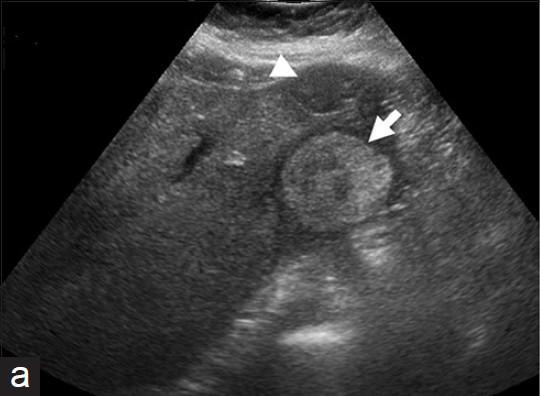

What is the sonographic appearance of Hepatic candidiasis?

Multiple

small

bull’s-eyes or target

lesions

Hypoechoic mass

echogenic core

What are the presenting symptoms of Hepatic candidiasis?

persistent fever and localized pain

What are the lab values that would suggest Hepatic candidiasis?

↑WBC